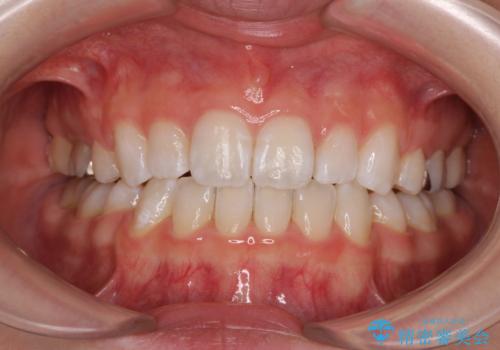

【モニター】口が閉じにくい 膨らんだ口元を抜歯矯正ですっきりと

- 前歯の出っ歯と口元の閉じにくさを気にして来院された患者様です。

口元を積極的に引っ込めるために、上下左右の小臼歯4本を抜歯することとしました。

4本の歯を抜歯したことで、飛び出していた口元が引っ込み、横顔が大きく改善されました。